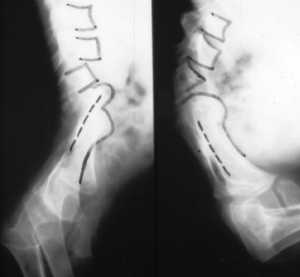

- scoliosis is better correlated with the presence of thoracic or thoracolumbar

vertebrae abnormalities (i.e. hemivertebra) than the lumbosacral defect.

However, scoliosis may occur when an asymmetrical spino-pelvic "joint"

is seen, or a part of the sacrum remains in the pelvis

- kyphosis is common finding, it's correlated with high level lumbosacral

agenesis and spino-pelvic instability. Kyphosis is often severe, reducing

the abdominal capacity and producing rib-pelvic "pseudo-joint"

CLASSIFICATION:

Renshaw (1978) classified sacral agenesis in four types:

- Type I: total or partial unilateral sacral agenesis

- Type II: partial sacral agenesis with a partial but bilaterally symmetrical

defect and a stable articulation between the ilia and a normal or hypoplastic

first sacral vertebra (most common).

- Type III: variable lumbar and total sacral agenesis with the ilia articulating

with the sides of the lowest vertebra present

- Type IV: variable lumbar and a total sacral agenesis, the caudal end-plate

of the lowest vertebra resting above either fused ilia or an iliac amphiarthrosis